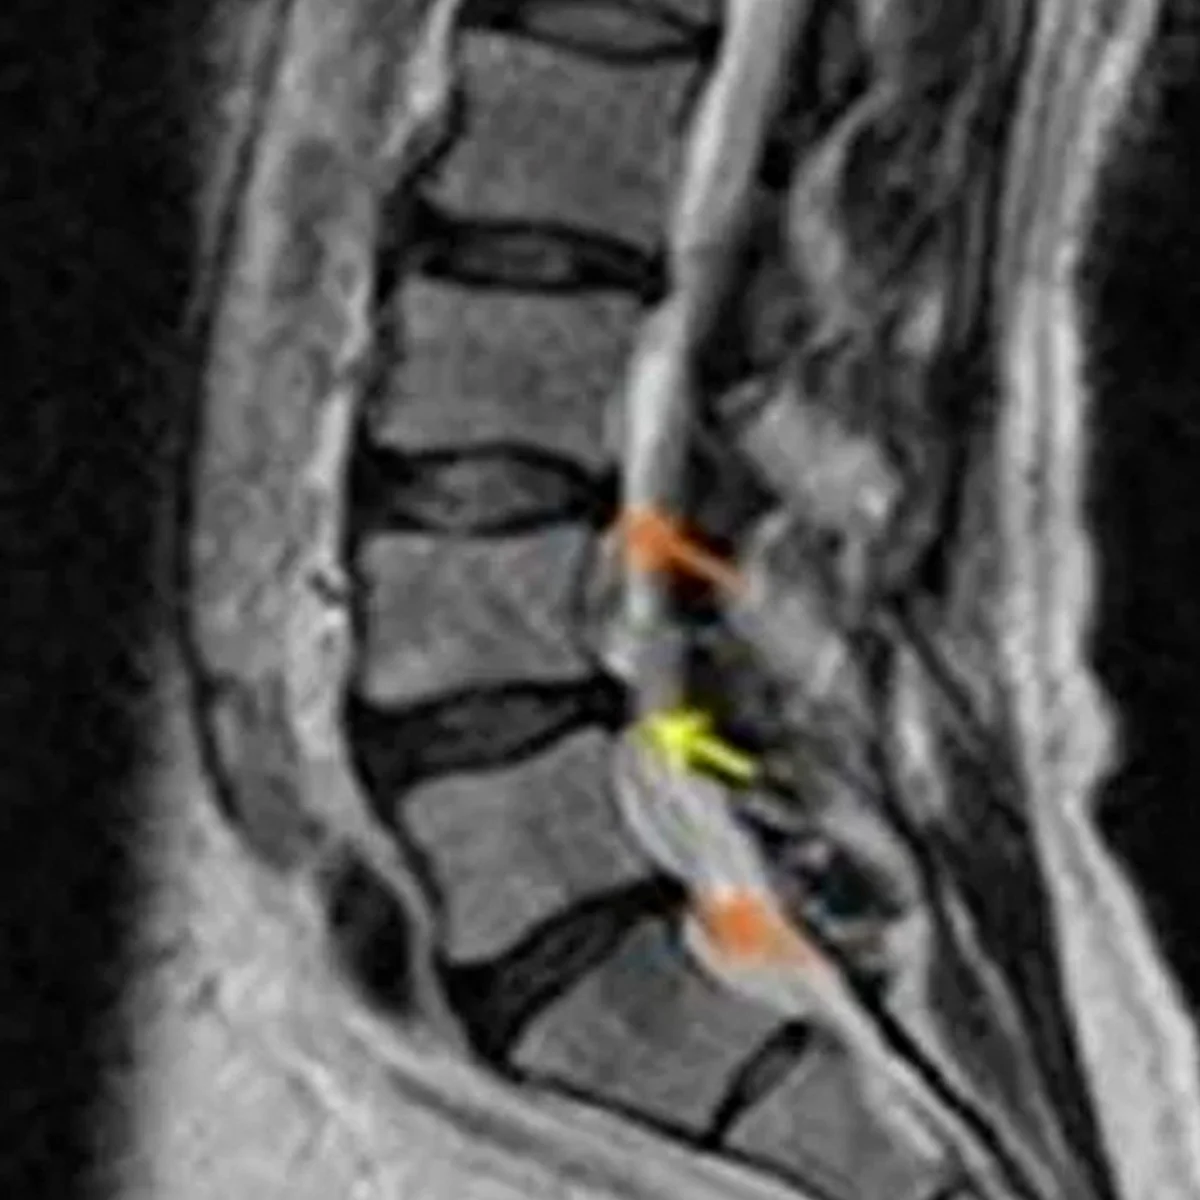

Hernias de disco

Esta condición puede causar dolor en la espalda, así como síntomas neurológicos como ardor, hormigueo entumecimiento y debilidad en las extremidades.

Este enfoque permite reducir los síntomas y mejorar la calidad de vida del paciente, siendo una opción efectiva para aquellos con hernias discales moderadas que buscan evitar procedimientos invasivos.